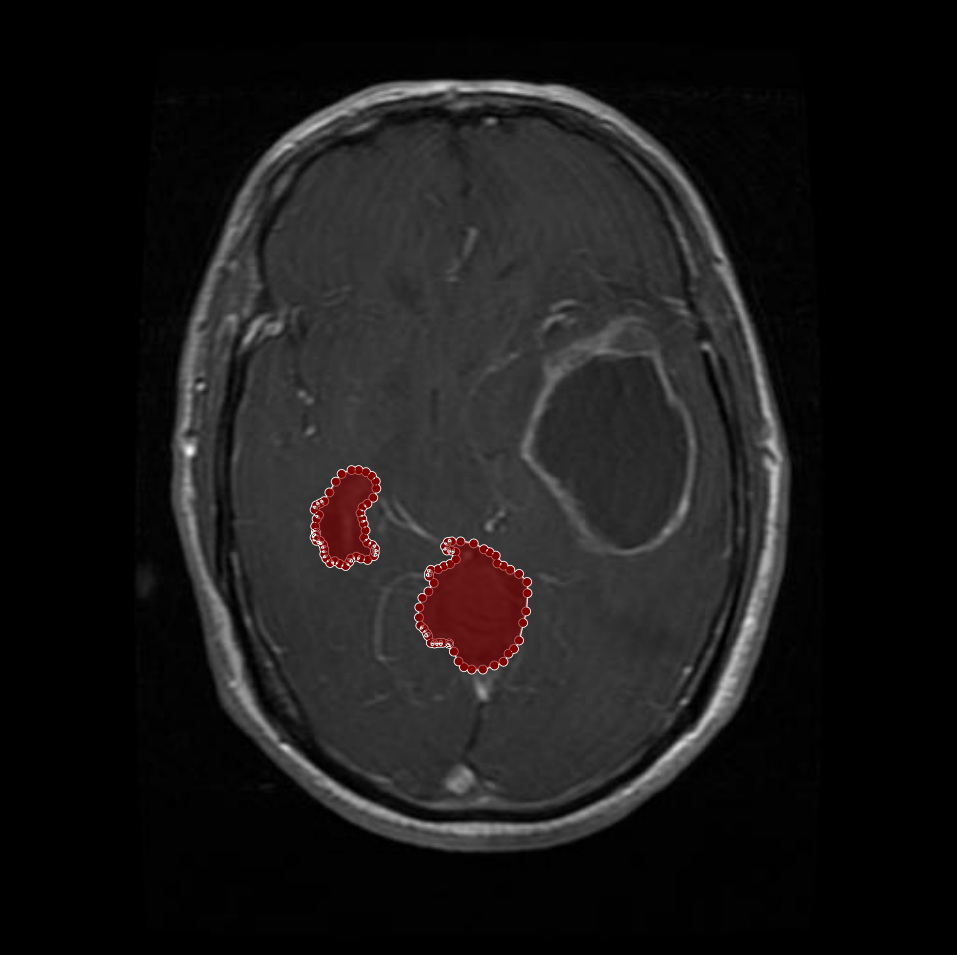

Figure 1: Samples of Glioma segmentation across different imaging planes

Glioma: Gliomas are irregularly shaped and often infiltrate surrounding tissues, presenting significant challenges for precise boundary definition. These complexities require robust segmentation techniques to capture their variable morphology. As shown in Figure 1, gliomas exhibit irregular and diffuse growth patterns, which are highlighted through annotated tumor masks.